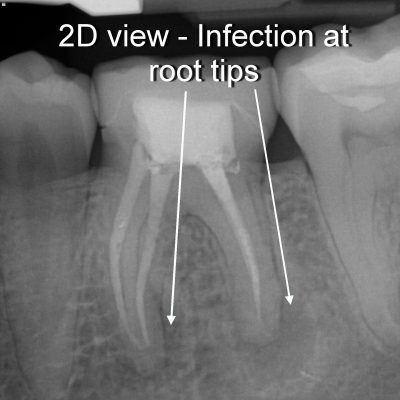

Liz was aware that there was an infection in her jaw. Despite her local dentist not being overly concerned with what they saw, we knew that this infection was putting her body at high risk for systemic infection. Liz flew to Portland and, after her BDC New Patient Experience, had her lower left first molar removed following our protocol. As you can see below, the 3-D x-ray is far superior in showing the infection that her root canal-treated tooth caused in her jaw bone.